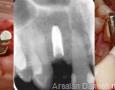

CBCT :

Pictures

Surgery